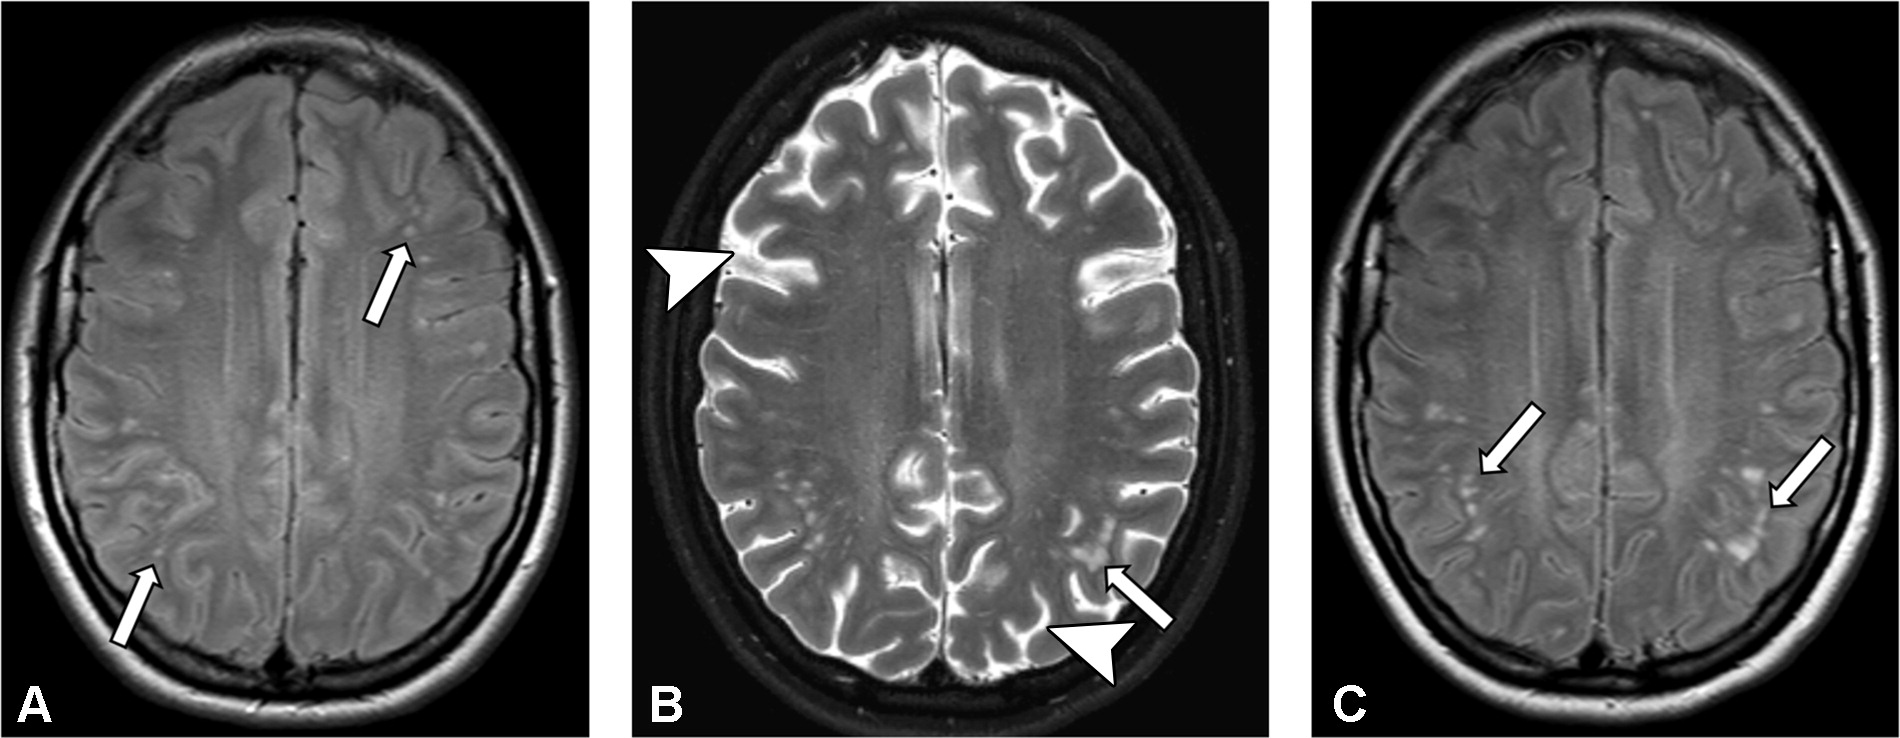

¿Cuales son los hallazgos típicos en resonancia magnética cerebral?

Generalmente causa atrofia de los lóbulos temporales.

Hiperintensidades corticales y subcorticales en FLAIR en los lóbulos temporales y cerebelo

Aquí un ejemplo (obtenido de Radiographics):

Se trata de una paciente femenina de 14 años, quien comienza con cefalea, alteraciones visuales, acatisia, y progresó a perdida de la conciencia.